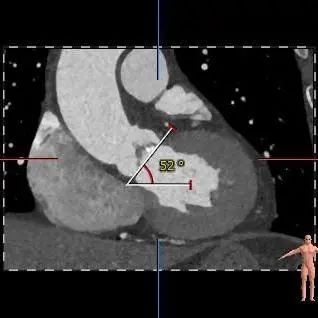

瓣环水平夹角46度

主动脉根部评估